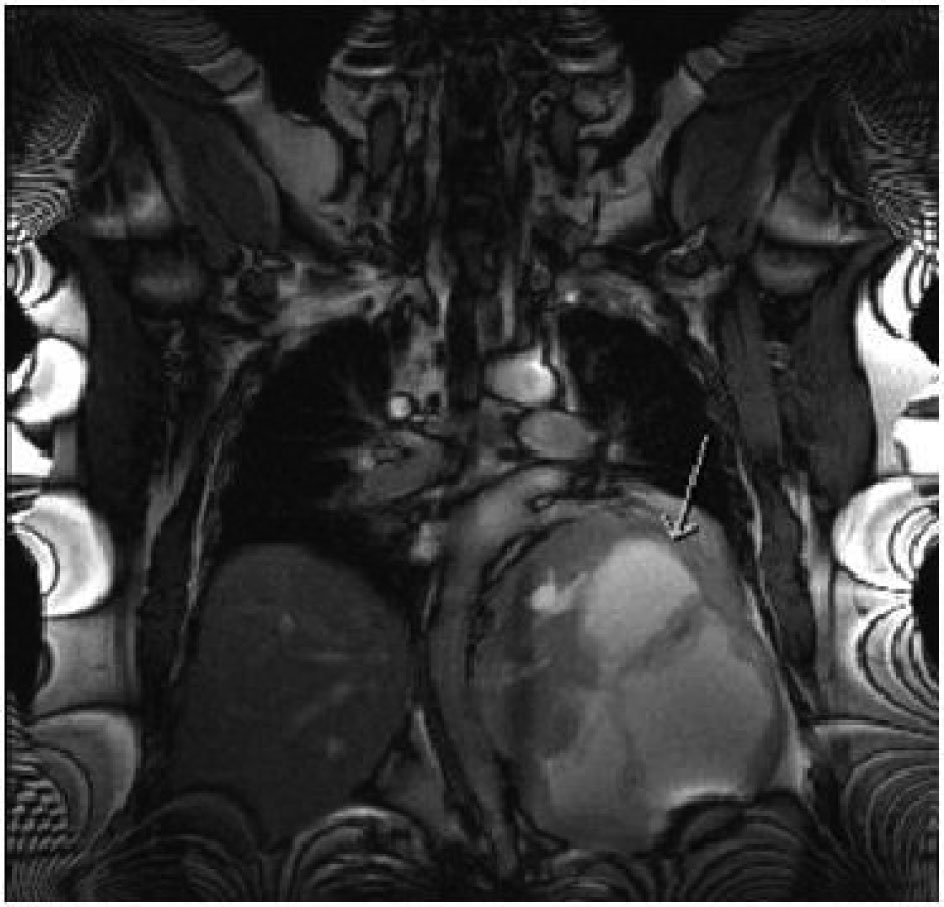

A 47-year-old obese man with severe mid-back pain for 6-months was found to have a large intra-thoracic mass on a routine plain film of the chest. A computed topography (CT) scan of the chest/abdomen/pelvis revealed a 20.5 × 15.5 × 16.0 cm heterogeneous mass in the left posterior mediastinum with effacement of the left lower lobe, left inferior pulmonary vein, displacement of hemi-diaphragm inferiorly and mediastinal structures towards to the right chest (Fig. 1). A magnetic resonance imaging (MRI) study revealed peripheral enhancement and internal necrosis (Fig. 2). CT-guided biopsy revealed a spindle cell tumor. Surgical resection was recommended.

![]() Click for large image | Figure 2. MRI features of the mass (arrow). |

The tumor was confirmed to be an ancient schwannoma based on unique histopathologic features of fibrous background with spindle cells, strong positivity for S-100 and negative for neurofilament protein, and epithelial membrane antigen [7]. The specimen lacked atypia, and pleomorphism (Fig. 1, 2) hence a benign tumor [7] despite its massive size.